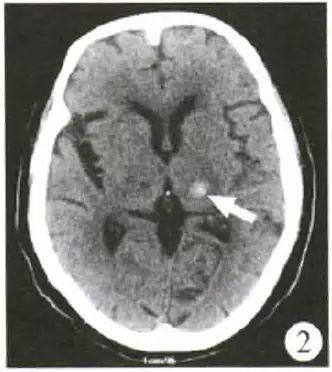

1、脑出血CT值40-45HU表示患者脑部存在较高密度的血肿,可能提示病情较严重,需结合临床情况综合判断。CT值是医学影像学中用于量化组织密度的单位,单位为亨氏单位(HU)。正常脑组织CT值约为25-45HU,而新鲜血液的CT值通常在40-80HU之间。

2、脑出血激活凝血系统后,血凝块形成,红细胞压积明显增加,CT上显示为高密度影,而腹腔出血往往为低密度的不凝血,原因为:呼吸运动、肠蠕动、腹膜的去纤维化纤维作用、创伤消耗凝血酶原等。一般不凝固的血液CT值约45HU,加上窗宽窗位和病变与邻近脏器密度对比的关系,腹腔出血往往显示为低密度。